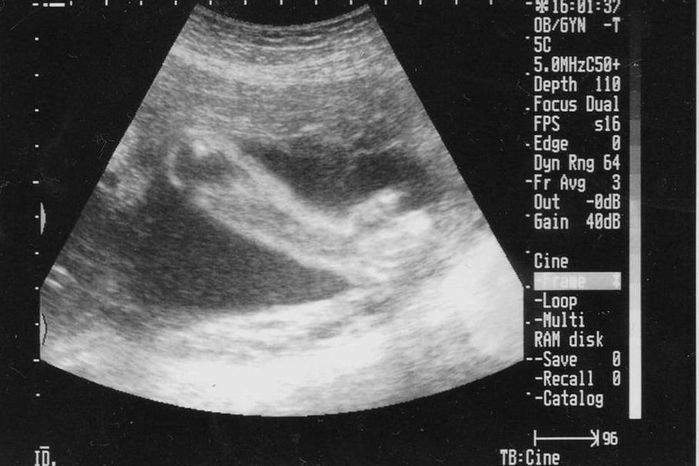

妊娠4週目のエコー写真

妊娠が確定した日、かねてからの憧れだった雑誌「たまごクラブ」を買いに行きました。妊娠経験や出産体験を見るため口コミサイト「ウィメンズパーク」に早速登録し、同じ月齢の妊婦さんのページから情報を集めました。初めて知る内容は興味深く、夜遅くまで読みふける毎日。